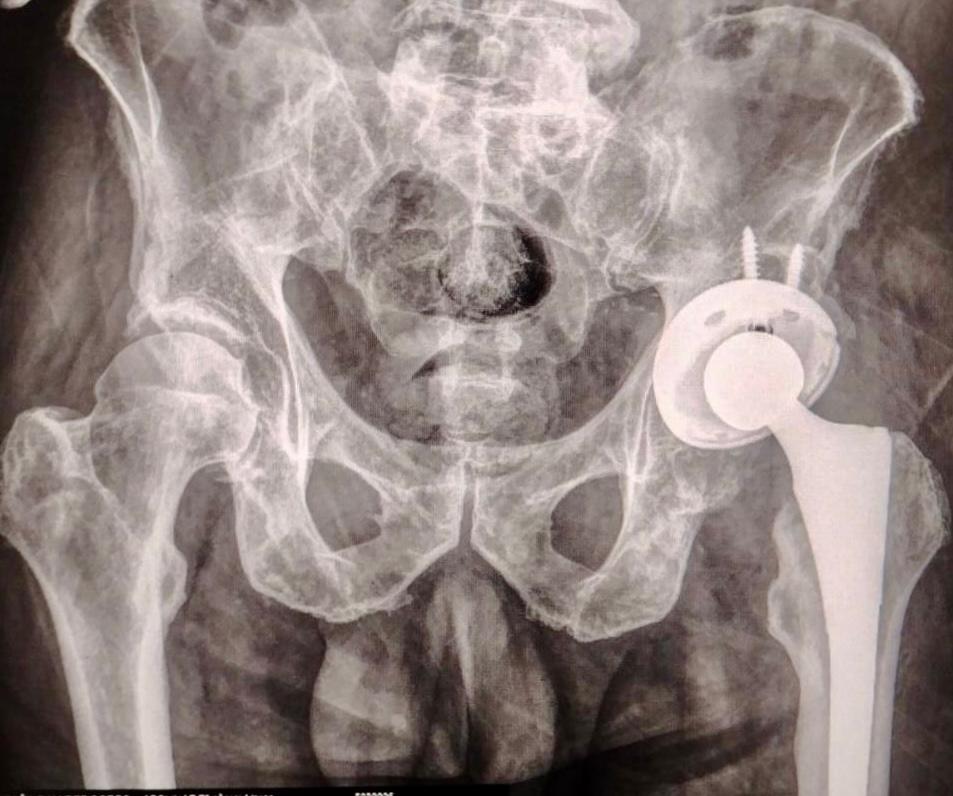

Puebla, Pue.- El Gobierno del Estado de Puebla a través del Instituto de Seguridad y Servicios Sociales de los Trabajadores al Servicio de los Poderes del Estado de Puebla (ISSSTEP), realizó con éxito y bienestar la colocación de la primera prótesis de cadera sin costo para el paciente, un nuevo hito en el fortalecimiento de sus servicios médicos de alta especialidad.

La intervención quirúrgica fue realizada por un equipo multidisciplinario altamente capacitado, bajo estrictos protocolos de seguridad y criterios clínicos de selección. Este procedimiento representa un paso significativo en la atención integral de padecimientos osteoarticulares, particularmente en pacientes con desgaste articular severo que afecta su calidad de vida y movilidad.

Este nuevo programa busca ofrecer alternativas de tratamiento quirúrgico de alto nivel, donde prioriza la seguridad del paciente desde la etapa preoperatoria, durante la cirugía y en el seguimiento posoperatorio. La implementación de tecnologías médicas avanzadas y el fortalecimiento de las capacidades humanas del personal quirúrgico son parte fundamental de esta estrategia.

Foto Especial